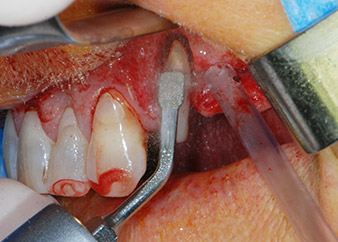

Prima di procedere al posizionamento dell'impianto, il tessuto infetto è stato rimosso dall'osso alveolare nel sito di impianto e attorno ai denti di appoggio con un attacco progettato per la sagomatura ossea e per la raccolta di frammenti ossei (Piezomed, attacco B5) (Figg. 6 e 7).

strumento piezoelettrico di raschiatura

Fig. 6: Il sito chirurgico è stato sbrigliato con uno strumento piezoelettrico di raschiatura per raccogliere frammenti ossei e modellare il tessuto osseo.

difetti ossei

Fig. 7: Dopo la pulizia, i difetti ossei mesiali rispetto al dente 27 e attorno alla radice del dente 24 erano chiaramente visibili.